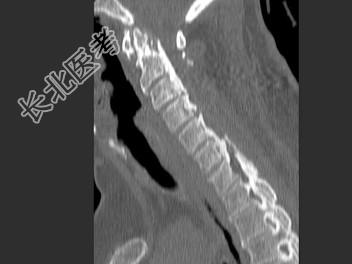

- 单项选择题女,58岁, 颈部疼痛,活动受限, 结合图像,最可能的诊断是 ( )

A、颈椎退行性变

B、颈椎结核

C、椎缘骨

D、椎间盘突出

E、局限性骨化性肌炎